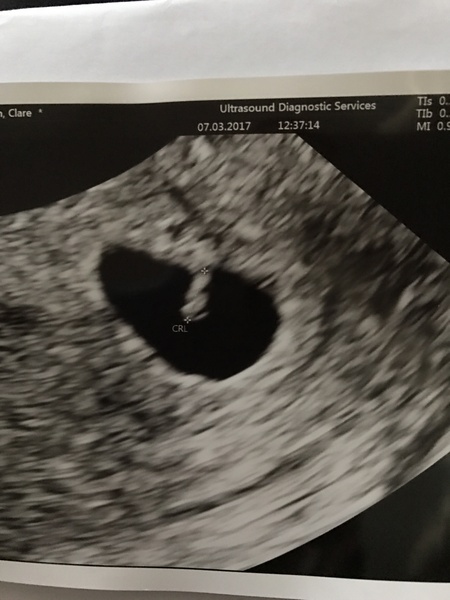

Rufus200 · 07/03/2017 20:41

Had my 6 wk scan today and there is one little heart beat in there. Very relieved there is a heart beat but also that there is only one. Quite shockingly the CL is on my left ovary that my Dr called dormant and only had a half the size it should of been follicle on it. I was sure it was going to be my right ovary that had done the job.